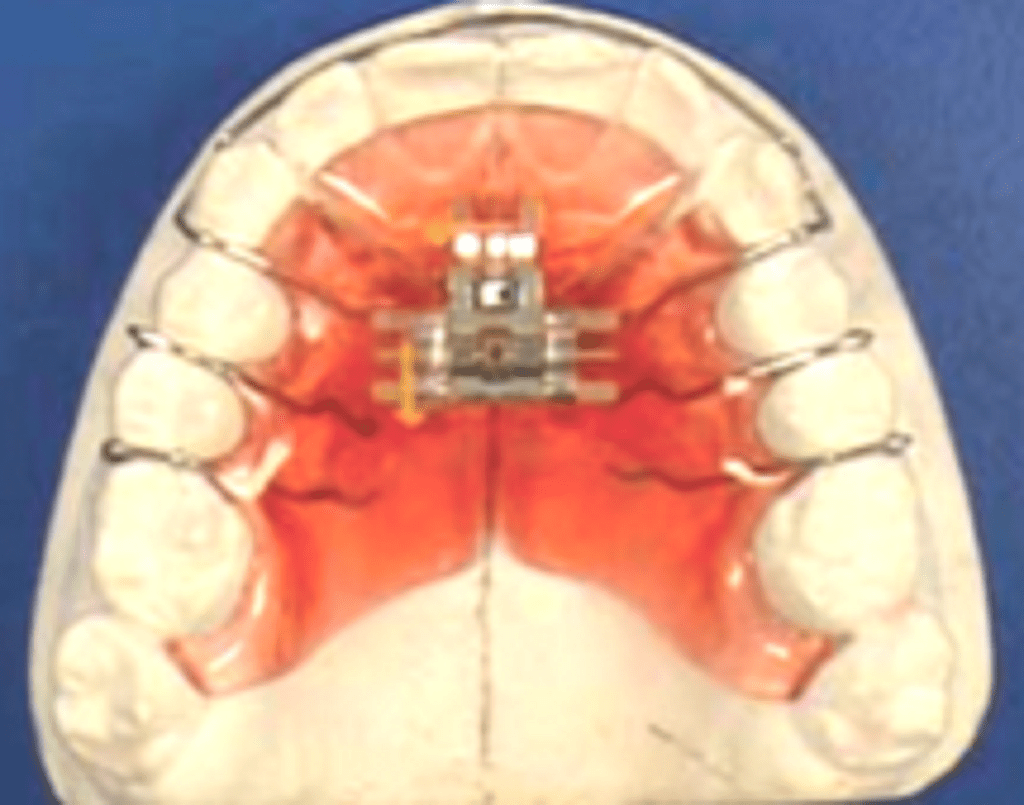

Bonded RME appliance

The bonded RME was first described by Cohen and Silverman in 1973. In bonded RME, instead of bands, metallic cap splints or acrylic covering is used.

Cast metal cap splints: Cast cap splint to all the teeth is prepared to which the screw is soldered. The entire assembly is cemented/bonded.

Acrylic splints: Thick gauge stainless steel wire is closely adapted around the posterior teeth from premolars to molars both buccally and palatally. The screw is soldered to the wire. Acrylic is covered over the occlusal, buccal and palatal occlusal third of all the posterior teeth. The assembly is cemented/bonded.

Advantages of bonded RME;

- Bonded appliances are useful in high-angle cases.

- The occlusal acrylic covering prevents the increase in mandibular angle by acting as a splint.

- Reduced posterior teeth tipping and extrusion.

- Provides bite block effect to facilitate the correction of anterior crossbite.